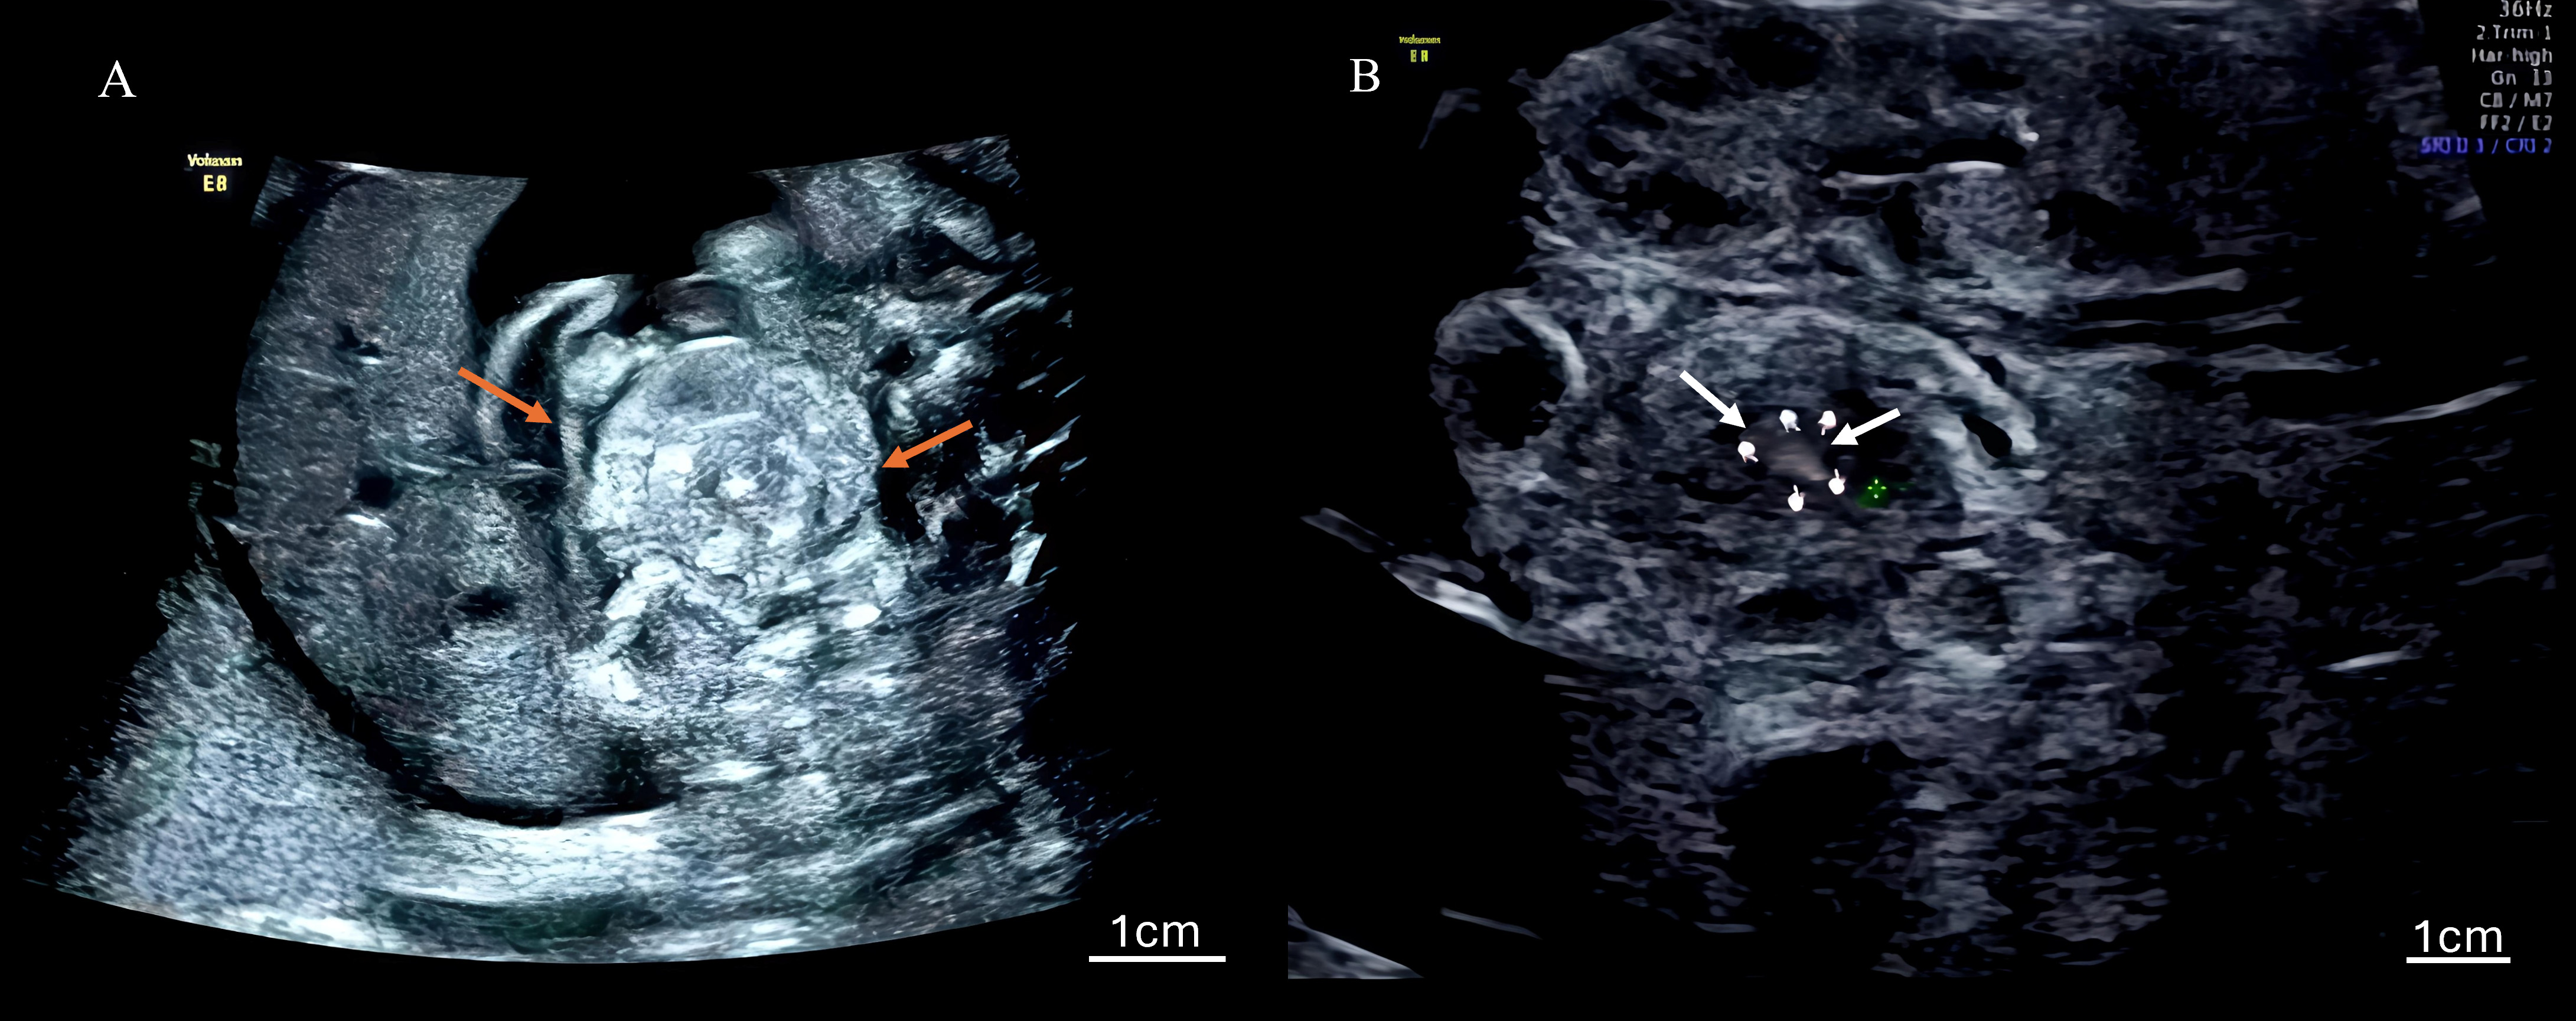

The ultrasonographic findings for all seven cases are summarized in Table 1, which details the gestational age at diagnosis and the presence of key signs. Table 2 quantifies the frequency of findings across all 27 examinations. Characteristic signs included the whirlpool sign (Fig. 1), annotated with arrows to highlight the spiral-shaped mass of dilated bowel loops), a spiral-shaped mass of dilated bowel loops, and the vascular spiral sign (Fig. 2A: 2D ultrasound; Fig. 2B: 3D ultrasound, with arrows indicating the mesenteric vein swirling around the mesenteric artery), observed in all cases (7/7). Nonspecific findings included bowel dilation (7/7), ascites (6/7), abdominal pseudocysts (2/7), coffee bean sign (2/7), hydramnios (1/7), and increased middle cerebral artery flow velocity (1/7). Among the 27 examinations, the detection rates were as follows: whirlpool sign, 20/27 (74.1%); vascular spiral sign, 20/27 (74.1%); bowel dilation, 23/27 (85.2%); ascites, 18/27 (66.7%); cystic abdominal masses, 5/27 (18.5%); coffee bean sign, 2/27 (7.4%); hydramnios, 3/27 (11.1%). Detailed case descriptions are provided below:

Fig. 2. Ultrasound images of the vascular spiral sign. (A) Two-dimensional color Doppler ultrasound of the vascular spiral sign, with the mesenteric vein swirling around the mesenteric artery, a direct indicator of volvulus; arrows highlight the swirling mesenteric vein, and a scale bar is included. (B) Three-dimensional power Doppler ultrasound enhances the visualization of the vascular spiral sign, observed in all cases. Arrows indicate the vascular spiral pattern, with a scale bar provided for reference. The little finger indicates the center of the whirlpool sign.